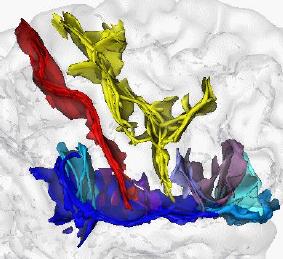

Functional MRI is based on the increase in blood flow to the

local vasculature that accompanies neural activity in the brain

This results in a corresponding local reduction in deoxyhemoglobin.

Since deoxyhemoglobin is paramagnetic, it alters

the magnetic resonance image signal

![[ppt]](img/ppt.jpg) How a brain get red and yellow spots:

How a brain get red and yellow spots:

An elementary introduction to functional Magnetic Resonance Imaging of fMRI